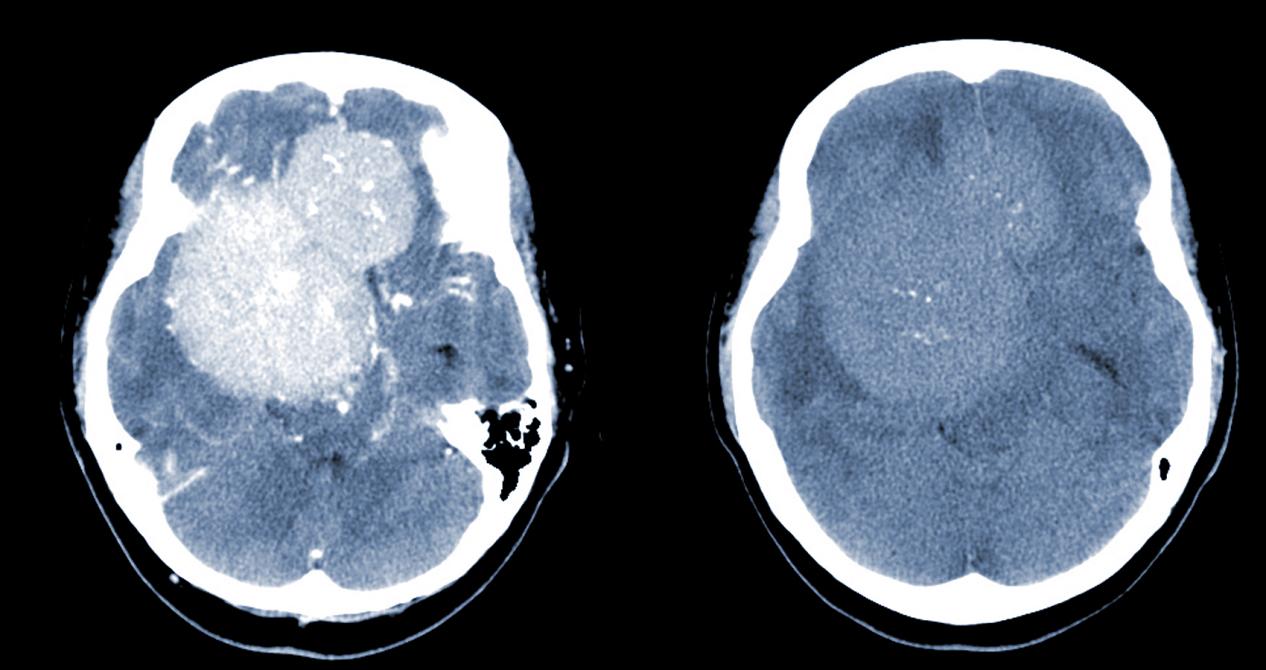

脑膜瘤的临床表现,昆明脑膜瘤医院哪家好-昆明医科肿瘤医院脑膜瘤是一种常见的颅内肿瘤,它通常发生在脑膜(覆盖脑部和脊髓的薄膜)上。由于它的位置和生长速度不同,其症状和表现也会因个体差异而有所不同。但是,一些常见的症状和诊断方法可以帮助医生和患者及时发现和治疗脑膜...

昆明脑膜瘤放射治方法,昆明脑膜瘤医院哪家好-昆明医科肿瘤医院脑膜瘤是一种危险的脑部肿瘤,治疗需要综合考虑患者的个体情况和病情,通常需要多种治疗方法的组合应用。以下是昆明治疗脑膜瘤的一些常用方法:手术切除手术切除是治疗脑膜瘤的首选方法。手术可以通过开颅手术或经鼻...

脑膜瘤放射治疗医院,昆明脑膜瘤医院哪家好-昆明医科肿瘤医院脑膜瘤是一种发生在脑膜(脑部外层覆盖的薄膜)上的肿瘤。它通常是良性的,但在某些情况下也可能是恶性的。脑膜瘤的治疗通常需要一个综合治疗方案,其中包括手术切除、放射治疗和化疗。放射治疗是一种常用的治疗方法,...